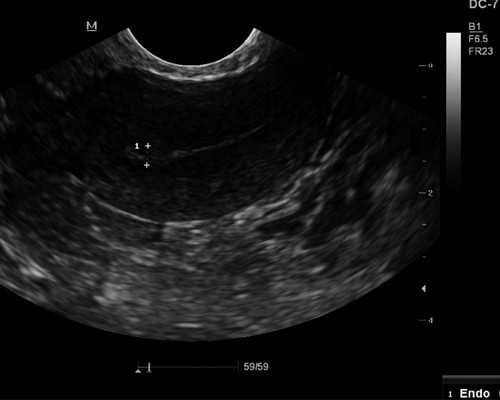

备孕攻略,B超监测排卵这样安排AA一个月怀孕

·有个姐妹找我帮忙看B超报告,卵泡18mm,医生建议明后天同房,她和老公异地,需要卡时间安排,有点担心这个时间晚了。·我看报告上子宫内膜已经去到10mm,达到排卵的厚度,判断当天可能会排卵,建议她当天和明天分别♥️一次。·后来她和我说,确实当天排了,她行动力也很强,当天安排老公过来♥️,祝她10月好......